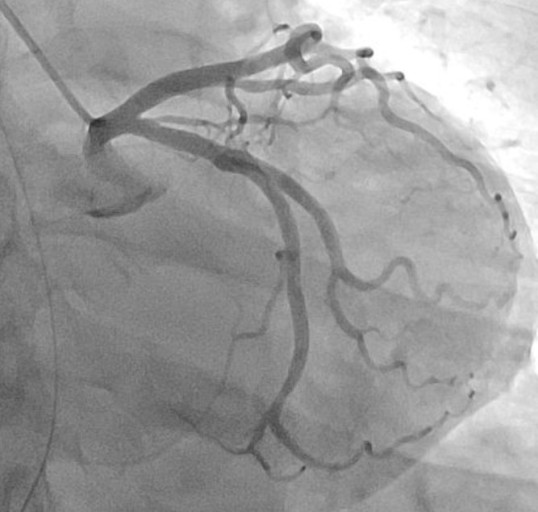

관상동맥 조영술은 심장 근육에 혈액을 공급하는 관상동맥의 상태를 진단하는 검사입니다. 흉통, 호흡곤란 등 협심증이나 심근경색증 등의 증상이 있는 환자에게 시행합니다.

- 도관을 통해 조영제를 주입하고 관상동맥을 촬영합니다.